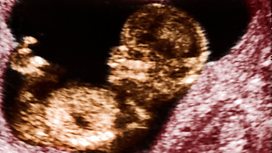

Plus it's our weekly meeting of 5 Live's Bump Club. We'll be busting those pregnancy myths, talking premature births and celebrating that special moment when you hear that first heartbeat.....

Bump Club member Laura on hearing her baby's heartbeat for the first time.